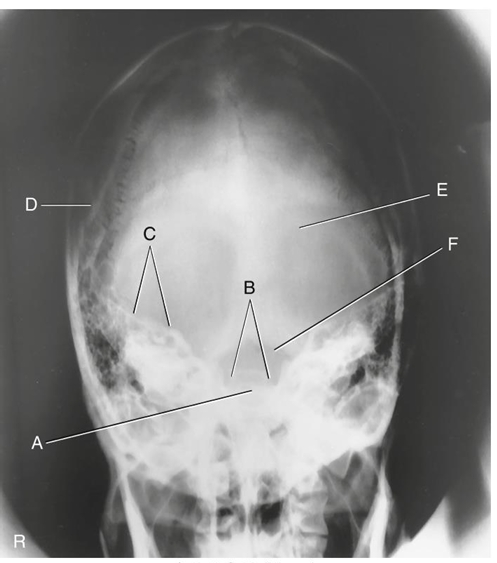

What is A?

supraorbital margin of right orbit (SOM)

What is B?

crista galli of ethmoid

What is C?

sagittal suture (post skull)

What is D?

lambdoidal suture (post skull)

What is E?

petrous ridges